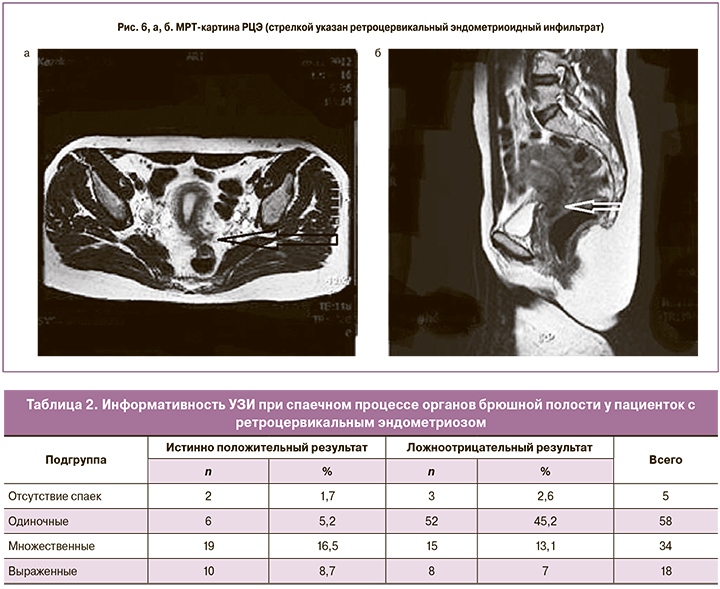

При РЦЭ у пациенток диагностирован эндометриоидный инфильтрат в позадиматочном пространстве с вовлечением шейки матки (рис. 6, а и б).

В нашем исследовании МРТ проведена 110 (91,7%) пациенткам c РЦЭ. Очаг РЦЭ был представлен в разных вариациях: в виде объемного образования с инфильтрацией задней стенки матки, широких связок матки, маточно-крестцовых связок, брюшины дугласова пространства с фиксацией кишки и заднего свода влагалища, распространением на стенку кишки с или без признаков прорастания.

Проведен сравнительный анализ данных МРТ и лапароскопии в зависимости от распространения РЦЭ, степени вовлечения в инфильтрат органов малого таза и выраженности спаечного процесса.